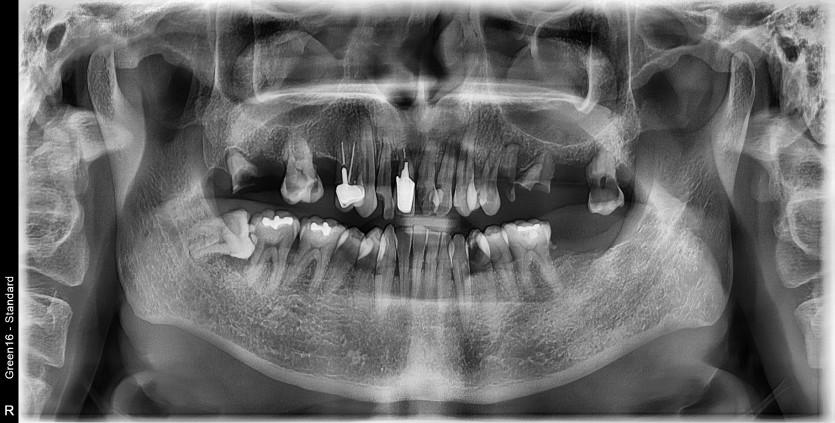

상악 전체 임플란트 증례입니다.

10개의 임플란트로 완성하였습니다.